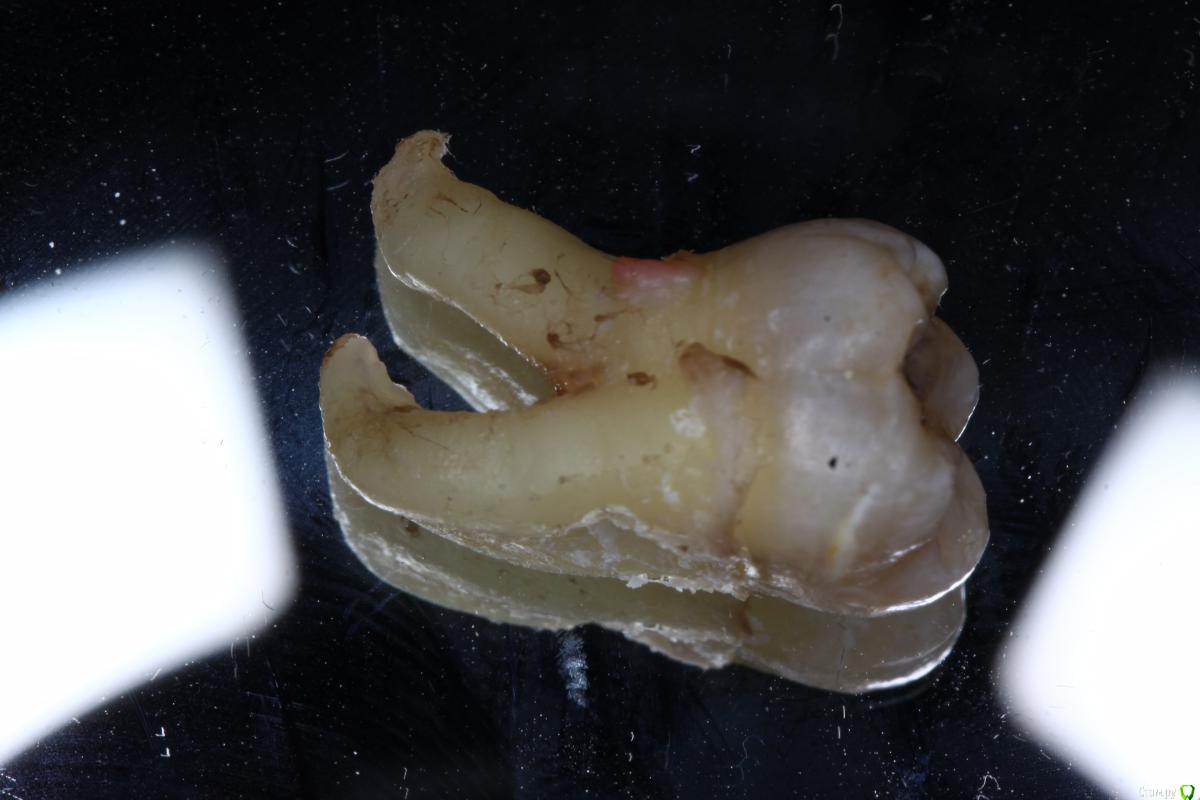

Павел7809 Опубликовано 22 сентября, 2016 Поделиться Опубликовано 22 сентября, 2016 Мои 5 копеек. Выглядит не страшно но любовь зуба с нижничелюстным нервов пощекотала нервы...попозже выложу срезы кт Ссылка на комментарий

Павел7809 Опубликовано 22 сентября, 2016 Поделиться Опубликовано 22 сентября, 2016 не знаю как в пост вставить.. 3 Ссылка на комментарий